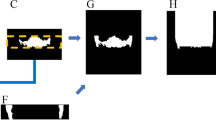

The objective of this work is to present a novel technique using convolutional neural network (CNN) architectures for automatic segmentation of sella turcica (ST) on cephalometric radiographic image dataset. The proposed work suggests possible deep learning approaches to distinguish ST on complex cephalometric radiographs using deep learning techniques.

The dataset of 525 lateral cephalometric images was employed and randomly split into different training and testing subset ratios. The ground truth (annotated images) represents pixel-wise annotation of the ST using an online annotation platform by dental specialists. This study compared convolutional neural network architectures based on fine-tuned versions of the VGG19, ResNet34, InceptionV3, and ResNext50 architectures to select an appropriate model for autonomous segmentation of the nonlinear structure of ST.